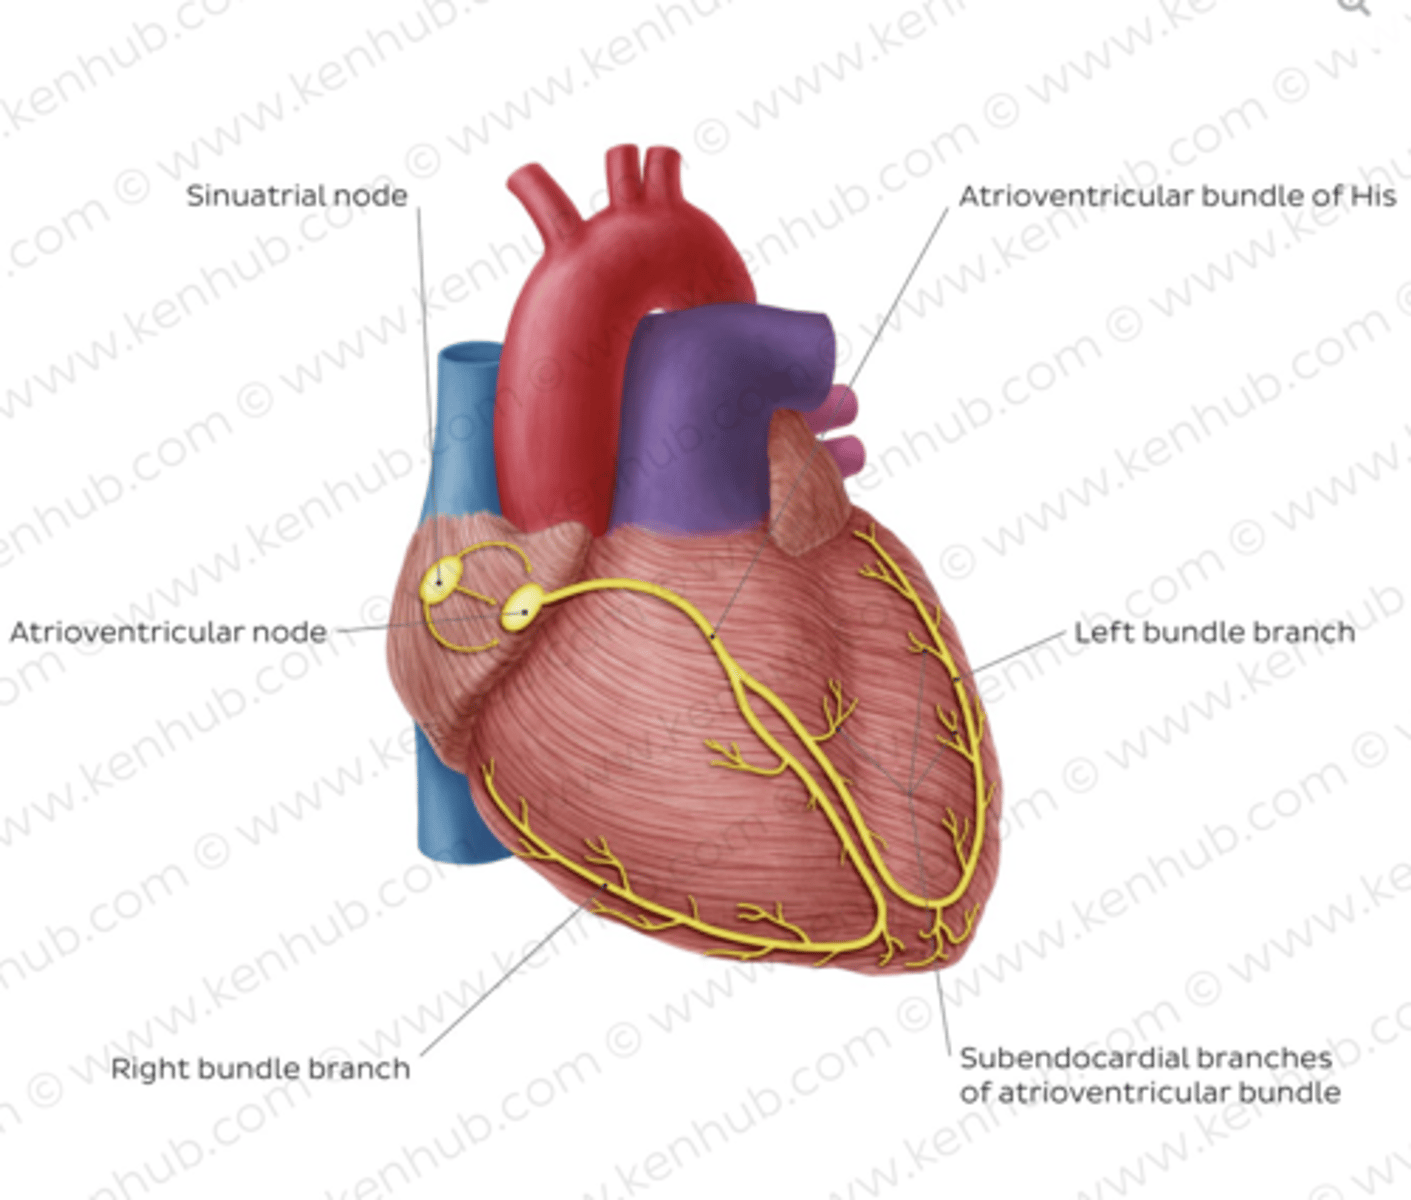

What allows the heart to contract by itself?

The heart possesses a specialized conduction system that gives it the autonomous capacity to contract, allowing it to pump by itself in a correct buffer.

What are the two conduction nodes of the heart conduction system?

. SA node (sinoatrial node)

. AV node (atrioventicular node)

What is the function of the sinoatrial (SA) node?

Pacemaker of the heart

Where is initiated the contraction of the SA node?

SVC (Superior Vena Cava)

passing through the atrium to the AV node

Where is the SA located?

upper wall of the right atrium,

at the junction where the superior vena cava enters

Where is the atrioventricular (AV) node located, and what follows it?

At the level of the atrioventricular septum,

AV node is followed by?

Bundle of Hiss that divides into two branches

Where does Bundle of Hiss ends?

Purkninje fibers

Describe the propagation of waves in the conduction system ?

. SA node sends the initial wave

Passes through the walls of the atria

. Ends at the AV node in the AV septum

. Travels along the Bundle of His

. Reaches Purkinje fibers in the walls of the ventricles

What role does the moderator band play in the conduction system?

Allows the wave to reach the papillary muscles, inducing their contraction simultaneously with that of the ventricles.

REMEMBER: PAPILLARY MUSCLES ACT THROUGH THE CHORDAE TENDINAE TO CONTROL THE TRICUSPID AND MITRAL VALVES.

What is the significance of the Bundle of His in heart conduction?

Branching to the right and left to ensure coordinated contraction of the ventricles.

What are the Purkinje fibers, and what is their function?

specialized conductive fibers in the walls of the ventricles that

facilitate rapid transmission of electrical impulses,

ensuring efficient and synchronized ventricular contraction.

How does the AV node contribute to heart rhythm?

Delays the electrical impulse from the SA node,

ensuring that the atria contract fully to transfer blood to the

ventricles before the ventricles contract.